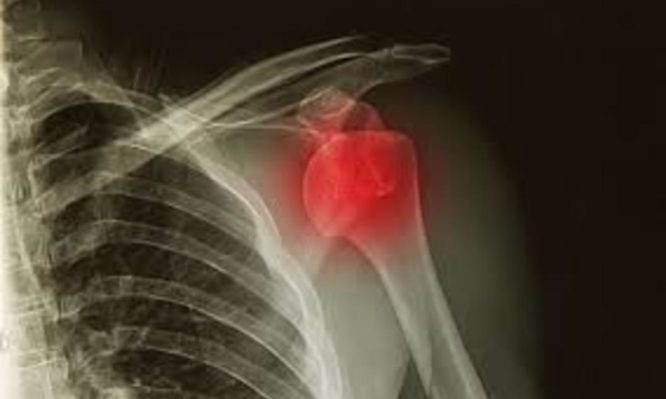

Τι να κάνετε αν πάθετε εξάρθρωση

Η εξάρθρωση είναι ένας τραυματισμός των αρθρώσεων με συνέπεια να φεύγουν από κανονικές τους θέσεις. Η αιτία είναι συνήθως...